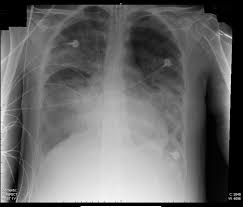

Rontgen Thorax Lunge Grunde Ablauf Bilder Praktischarzt

Rontgenuntersuchung Des Brustkorbes Zeigt Herzvergrosserungen